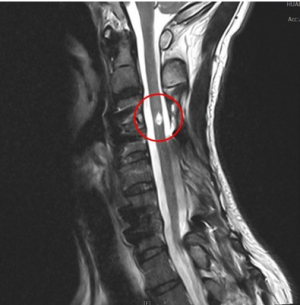

晶片刺激治療 脊損傷友找回下肢行動力

「能醒能走」是花蓮慈濟醫院神經外科中西醫復健合療團隊積極努力的重大發展方向,其中利用脊髓電刺激療法改善脊髓損傷病友的症狀,是花蓮慈院近三年來發展的技術重點之一。神經外科主任蔡昇宗表示,在脊椎適合位置植入神經刺激器,透過電極發送微量電流到神經節控制的相關肌肉群,能幫助嚴重腦損傷及脊髓損傷的患者,從意識不佳到逐漸清醒,讓全身癱瘓無法行走的病人再次站起來,並練習走路,促進病人生活自理的能力,找回生命的尊嚴,也減輕照顧者的壓力。